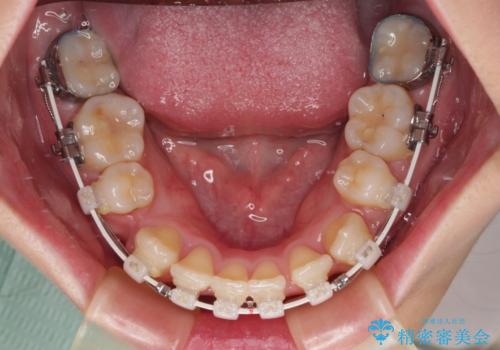

- 矯正装置

- 審美装置

- 八重歯やクロスバイトを気にして来院された患者様です。

口元の突出感はありませんでしたが、デコボコが強く、非抜歯矯正とすると出っ歯仕上がりとなる可能性があったため、上下左右の第一小臼歯4本を抜歯し、ワイヤー装置にて矯正治療を行うこととしました。